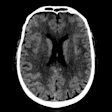

Head and Neck Radiology: Page 9